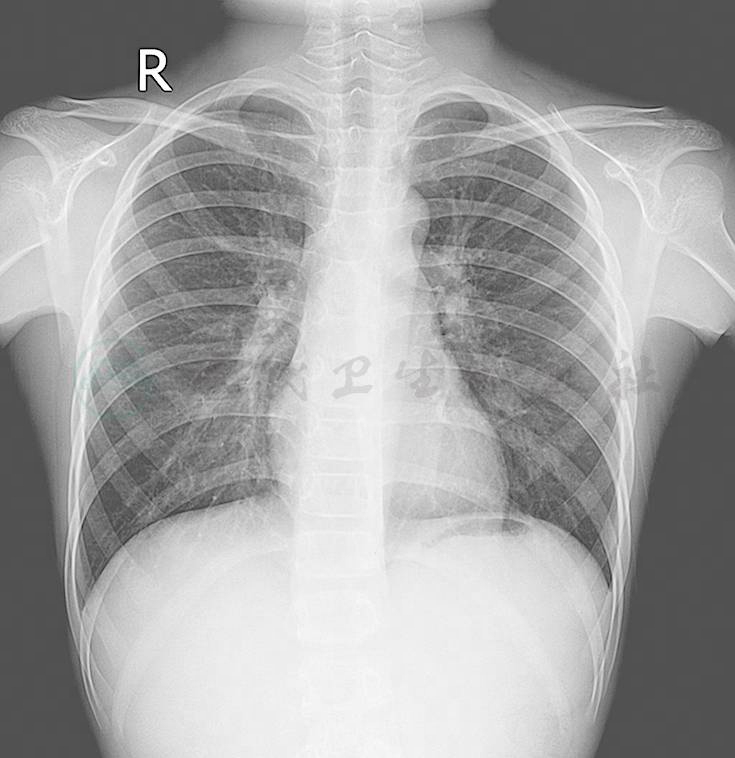

密度,肺野第二前肋间最高密度1.70 ± 0.05;肺门密度(背景均匀无骨骼重叠处)0.75 ± 0.05;肺周边部密度(近胸壁1cm处与单肋骨重叠处)0.65 ± 0.05;心影部密度(左心影内肺纹理处)0.40 ± 0.02;膈下部(肝肺重叠部)0.35 ± 0.02。对比度,肺野(最高密度)与肺门的对比度0.8 ± 0.15;气管(透亮区)与附近纵隔的对比度> 0.05;肺野(最高密度)与气管分叉下纵隔的对比度1.30 ± 15;肺野(最高密度)与邻近肋骨的对比度0.3 ± 0.10;锐利度,肋骨和锁骨骨棱,心脏与横膈边缘锐利;肺纹理边界清晰。颗粒性,肩胛骨下方软组织无颗粒状阴影,即无照片斑点影(图1~图4)。

图2  胸部侧位

图4  胸部侧位图像